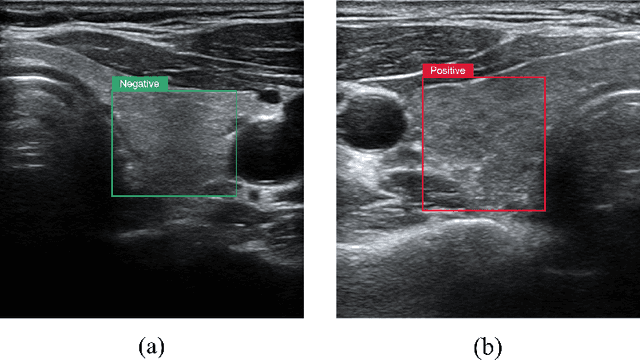

Abstract:Graves' disease is a common condition that is diagnosed clinically by determining the smoothness of the thyroid texture and its morphology in ultrasound images. Currently, the most widely used approach for the automated diagnosis of Graves' disease utilizes Convolutional Neural Networks (CNNs) for both feature extraction and classification. However, these methods demonstrate limited efficacy in capturing texture features. Given the high capacity of wavelets in describing texture features, this research integrates learnable wavelet modules utilizing the Lifting Scheme into CNNs and incorporates a parallel wavelet branch into the ResNet18 model to enhance texture feature extraction. Our model can analyze texture features in spatial and frequency domains simultaneously, leading to optimized classification accuracy. We conducted experiments on collected ultrasound datasets and publicly available natural image texture datasets, our proposed network achieved 97.27% accuracy and 95.60% recall on ultrasound datasets, 60.765% accuracy on natural image texture datasets, surpassing the accuracy of ResNet and conrming the effectiveness of our approach.